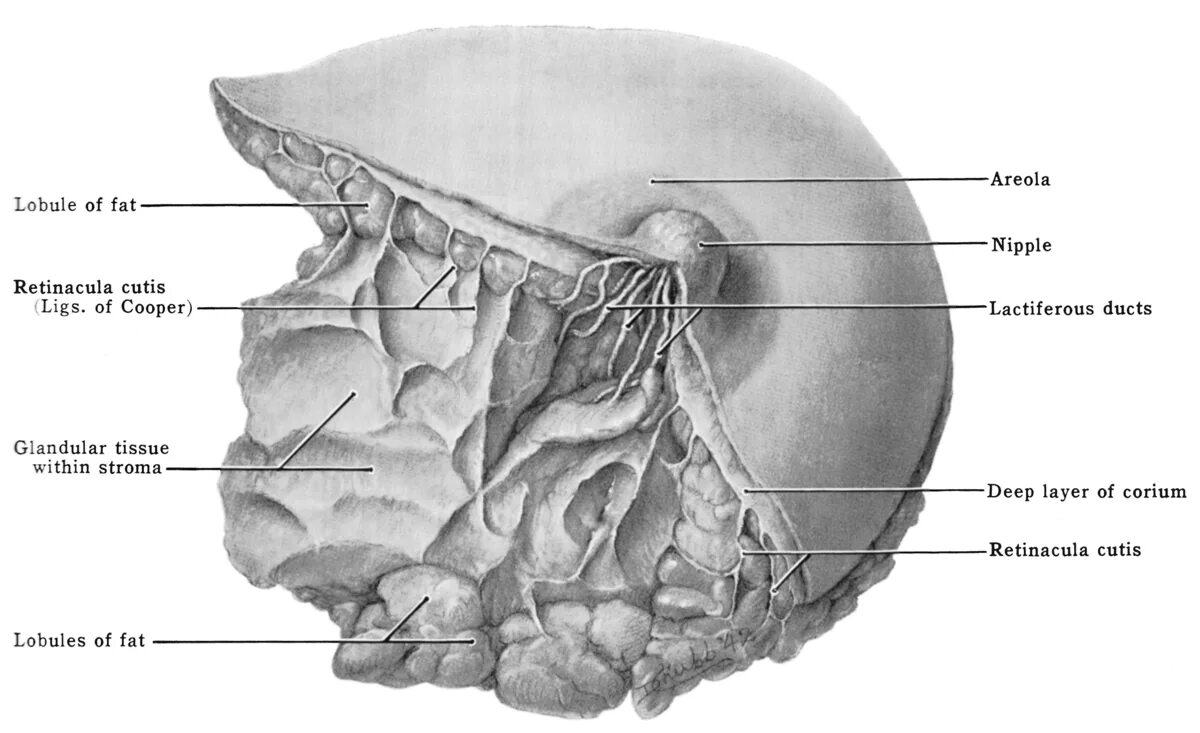

Labeled as